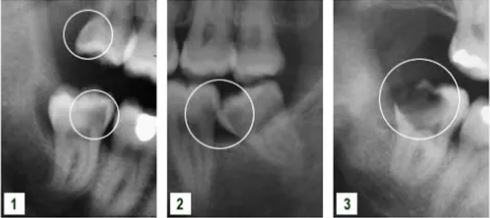

Các nang (vùng mũi tên) có thể phát triển từ biểu mô xung quanh răng khôn mọc ngầm. Nang gây nên hiện tượng phá hủy xương hàm, vùng phá hủy rộng gây xô đẩy và tổn thương các răng bên cạnh. Phẫu thuật loại bỏ răng khôn và bóc tách nang là rất cần thiết để ngăn chặn hiện tượng tiêu xương.

Mộ số trường hợp hiếm gắp khối u gấy ra do răng khôn mọc ngầm có thể gây gẫy xương tự phái nếu kích thước khối u lớn.